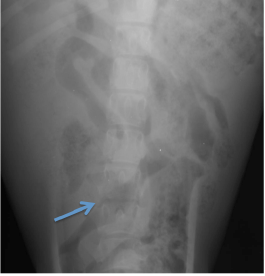

Herói, canídeo Pastor Alemão, macho inteiro de 4 meses, apresentado à consulta por prostração e dificuldade na marcha. Os proprietários reportaram relutância ao movimento associada a dor, fraqueza e prostração que vinha a agravar-se há uma semana. À palpação abdominal era notável algum desconforto. No exame fisico apresentava febre e alteração de postura compatível com dor, o que se designa de cifose. No exame neurológico o Herói apresentava-se alerta, com paraparésia e hipometria dos movimentos dos membros posteriores. À palpação revelava uma atrofia muscular pronunciada dos mesmos e dor lombar acentuada. Exibia atraso na resposta do posicionamento proprioceptivo, na reação de salto e reação extensora de ambos os MP, assim como hiporreflexia no reflexo patelar bilateral. Realizaram- se radiografias à sua coluna que revelaram alterações do contorno vertebral de das vértebras lombares L5 e L6 por erosão da placa terminal caudal de L5 e cranial de L6, sinais de esclerose ligeira das margens ventrais das mesmas vértebras, diminuição ligeira do espaço intervertebral. Tendo em conta a história e achados o diagnóstico presuntivo foi de discoespondilite que acabou por ser confirmado por TAC. O Herói esteve internado mais cinco dias com tratamento e suporte incluindo antibioterapia especifica e teve alta alguns dias depois.